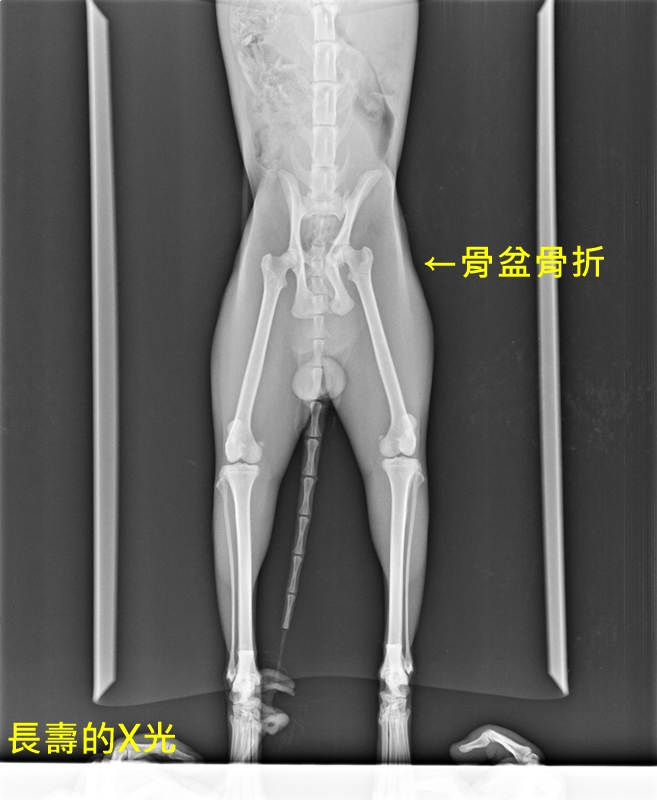

這畫面太驚悚,我真的超怕!但是黑白貓不斷對我大叫,顯然還活著。總之先把他撈進塑膠袋,先送到醫院再說吧。在X光掃描下,發現肋骨的 5、6、7、8、12、13 骨折,總共 6 根肋骨斷掉,骨盆骨折,肺氣腫及皮下氣腫,心肺功能問題,腹部可能有內出血。抽血檢查發現貧血,白血球升高到 5 萬左右,伴隨胰臟炎、肝指數升高,此外還有上呼吸道問題。醫師希望先觀察三天,如果能撐過危險期,再看要不要治療。貓咪當天有自行排尿,算是個好消息。從檢查結果來看,貓咪應該是左側被車撞上。

便便很粗,不知道是否能通過受損的骨盆,順利排便。